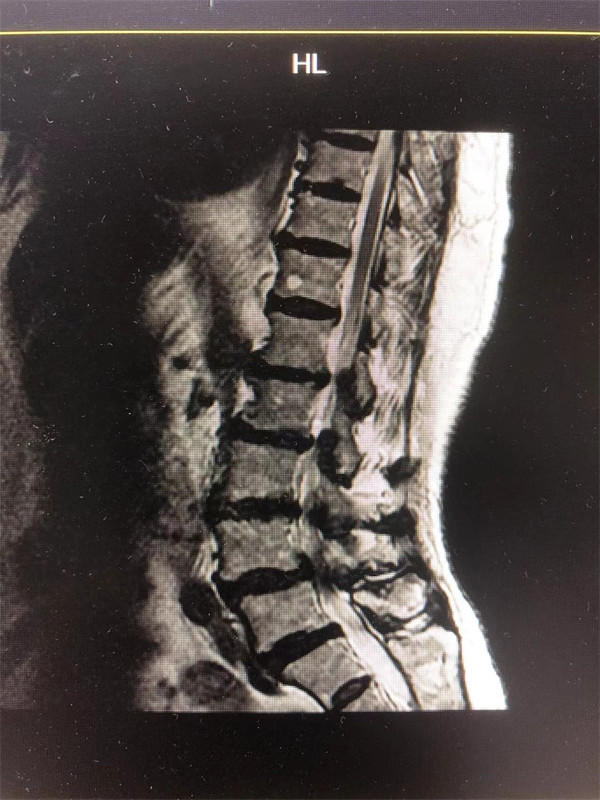

手術(shù)前↓

戈主任仔細(xì)詢問阿婆病情癥狀,綜合查體及MRI片情況,認(rèn)為阿婆有明顯的腰椎滑脫,腰椎管狹窄,這是引發(fā)阿婆病痛的主要因素。

阿婆曾在院外多家醫(yī)院就醫(yī),被診斷為腰4椎體滑脫癥、腰椎管狹窄癥、腰椎間盤突出癥,外院予以止痛、理療、針灸等各種保守方式治療,病情未見明顯改善。